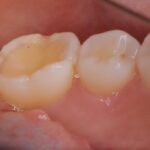

正中の不一致とクロスバイトをマウスピース矯正で綺麗に修正

インビザライン(全体矯正)+ホワイトニングコース+セラミック治療の症例

過去にワイヤー矯正で治せなかったクロスバイト。インビザライン(全体矯正)とホワイトニングとセラミック治療で綺麗な笑顔へ。

・費用:726,000円(税込) ※ホームホワイトニングと右上6番ジルコニアクラウン含む

・治療期間:15ヶ月

・通院回数:10回

・32歳女性

-リスクと副作用-

・長時間マウスピースを装着するため、むし歯や歯周病のリスクがある。治療後はリテーナーを装着しないと後戻りしてしまうリスクがある。

・ホワイトニング剤の影響で知覚過敏が起こる可能性がある。色が徐々に戻る可能性がる。

・セラミック:過度な衝撃によって割れることがある。